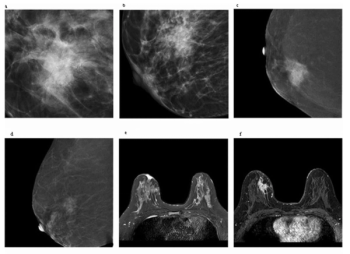

Is the Kaiser Score More Effective than BI-RADS for Assessing Contrast-Enhanced Mammography and MRI?

For women with breast-enhanced masses, Kaiser scoring (KS) demonstrated a 20 percent higher AUC than BI-RADS classification for contrast-enhanced mammography (CEM) and was comparable to KS for breast MRI.